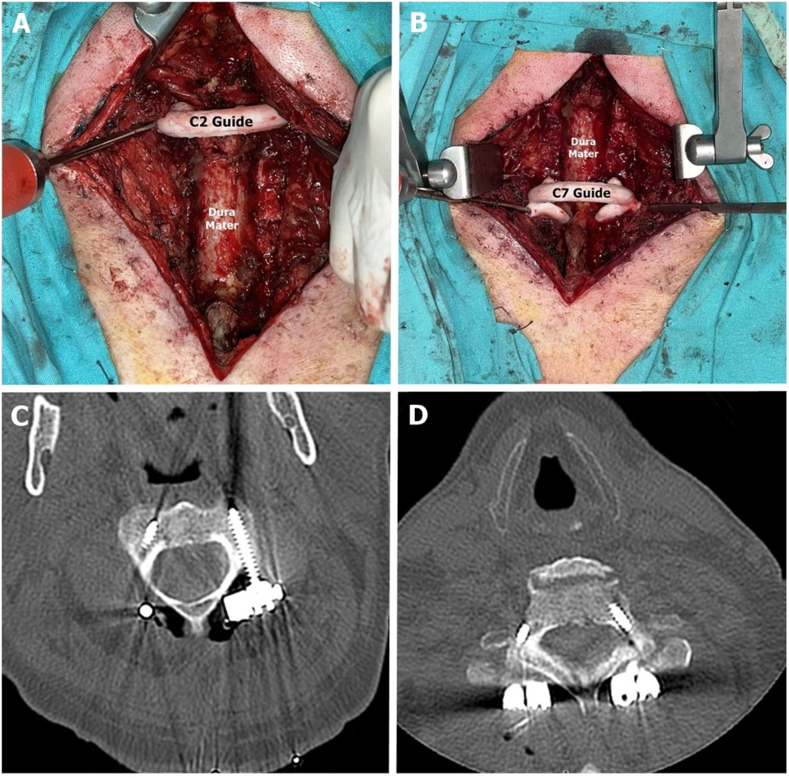

Case report: A 62-year-old male with a cervical spinal injury underwent emergency decompression at an external facility. Subsequent imaging revealed iatrogenic instability due to multi-level laminectomies (C3-C6). Preoperative CT data were processed using software (Mimics v14, MeshMixer) to design patient-specific templates, printed with a 3D Ultimaker 2 printer. These sterilized templates were used intraoperatively for navigation, aiding in transpedicular screw placement at C2, C7, and T1 levels, with lateral mass screws placed for C3-C6 using a freehand technique.

Results: Intraoperative fluoroscopy confirmed accurate screw placement with no vertebral artery injury or malposition. Postoperative CT validated precise alignment, and no hematoma or complications were observed. The use of 3D templates reduced operative time and radiation exposure compared to traditional methods.